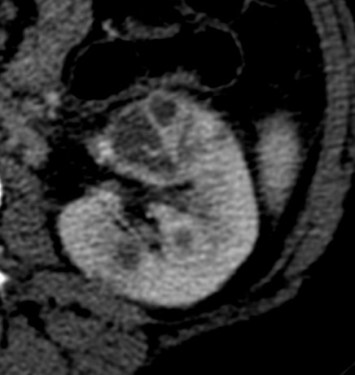

Se procede a realizar TC abdomino-pélvico con contraste en fase nefrográfica y excretora:

Conclusión: se nos presentó un caso de un paciente con una sospecha de infección renal complicada ya que tras cuatro días de tratamiento antibiótico no hubo mejoría. Ante los hallazgos observados en TC, podemos establecer el diagnóstico de pieloureteritis renal izquierda con signos de hidroureteronefrosis leve hasta vejiga.

- Protocolo: TC abominopélvico sin y con contraste en fase nefrográfica (70 seg) +/- fase tardía ( a los 7 – 10 min) solo si se sospecha obstrucción.

- TC con contraste: Las áreas afectadas del parénquima aparecen como zonas con baja atenuación debido al edema. Las áreas hiperdensas son menos frecuentes y corresponden a focos de hemorragia. Estos hallazgos son mejor valorables a través de la aplicación de contraste, ya que un TC en vacío pueden pasar desaprecibidas.